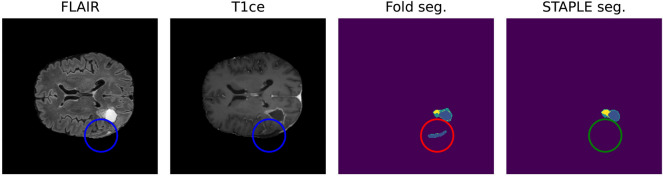

Finally, STAPLE algorithm was used to evaluate and compare all output segmentations returned by the fivefold cross-validation [28] (Fig. 3).

Fig. 3.

Positive effect of STAPLE fusion for resection cavity segmentation. Results obtained from the fivefold cross-validation process (fold seg.) are merged by the STAPLE algorithm to obtain a final result (STAPLE seg.). The figure shows, as an example, how the STAPLE convergence is able to recognize oversegmentation of a hypointense region misclassified as resection cavity (blue: cavity, yellow: enhancing, green: whole)

Post-processing

Post-processing was applied in order to bring back the three overlapping regions to the default ones of edema, ET, and RC. Specifically, if the probability of a voxel being classified as either GTV or edema was ≤ 0.45, it was classified as background. Else, if the probability of being classified as GTV was ≤ 0.4, then the voxel was classified as edema. If the probability of being a GTV voxel was > 0.4 and the same held for the probability of being classified as RC, then the voxel was identified as such (or simply ET if the latter was not true). Moreover, any connected component identified as RC smaller than 16 voxels with an overall probability smaller than 0.9 was ignored and classified as ET instead (Fig. 3). These values were determined via a grid search on the 5 folds, starting from the parameters proposed by Futrega et al. [25] for the preoperative case.